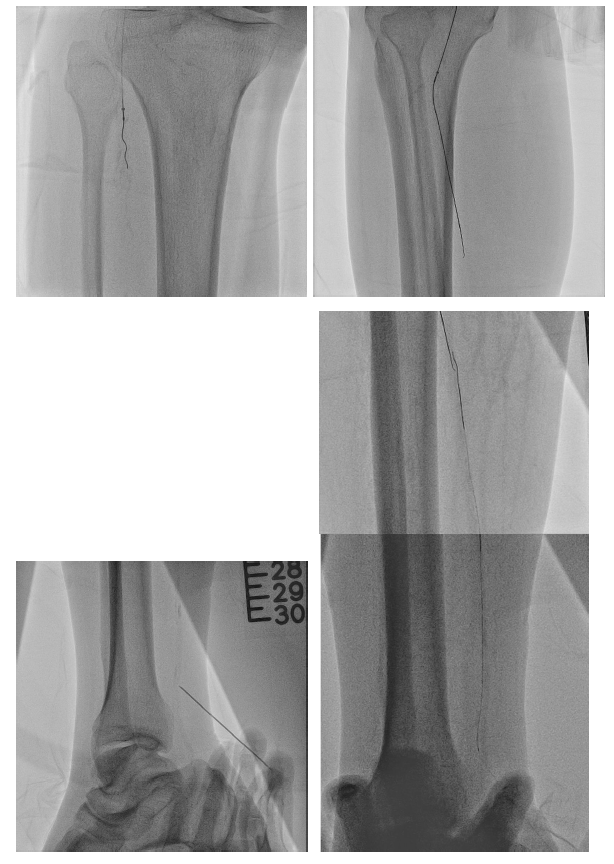

From a right femoral approach to RCFA, we used 0.014" GLADIUS GW with Oscar¢ç multifunctional peripheral catheter initially and changed wire to ASTATO XS40 GW to wiring the infrapopliteal CTO targeting the posterior tibial artery. However, even under strong support of Oscar¢ç multifunctional peripheral catheter, we still could not antegrade wiring through. Therefore, we performed a retrograde puncture to distal posterior tibial artery. We used 0.014" GLADIUS GW with CXI microcatheter and Knuckle technique to retrograde approach proximal posterior tibial artery. Successful rendezvous was achieved, confirming passage through the CTO segment. Balloon passage through the distal PTA lesion was difficult due to tight stenosis. So, several attempts with needle cracking technique on the distal PTA lesion was done, following serial balloon dilatation to PTA. Distal PTA perforation occurred secondary to excessive needle cracking. Several attempted hemostasis were performed following distal PTA perforation but in vain. A covered stent was deployed to seal the distal PTA perforation. Final angiography showed successful revascularization to PTA CTO.